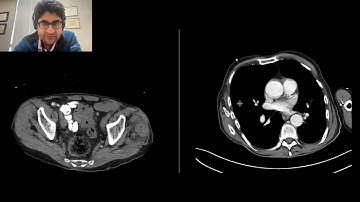

Abdominal CT Tutorials - Closed loop small bowel obstruction